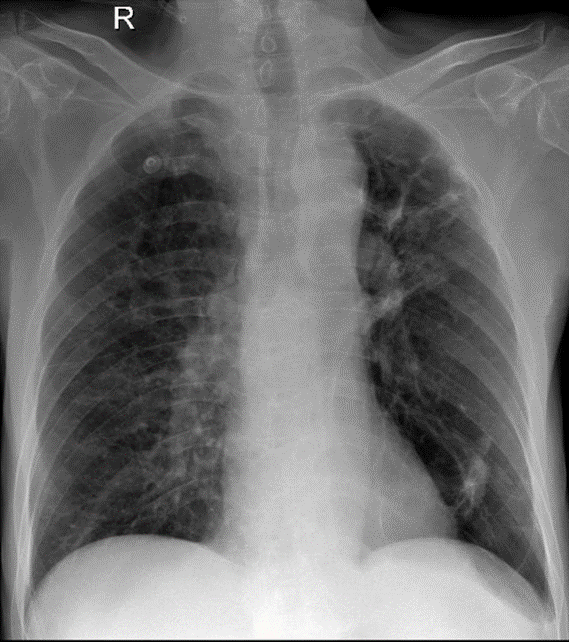

Hãy phân tích tình huống Nam 81 tuổi -CĐ: đợt cấp COPD nhóm d, cao huyết áp, loãng xương

1-Xơ vôi rải rác phổi (T), thùy trên > thùy dưới 2-Dày dính màng phổi (T)